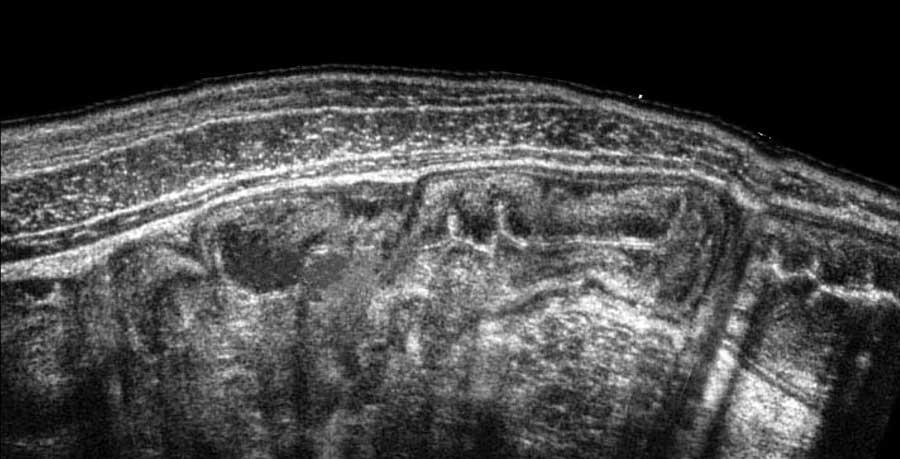

Các máy siêu âm hiện đại cung cấp hình ảnh độ phân giải cao của đường tiêu hóa, như ở bệnh nhân này với hình ảnh dày lớp niêm mạc và dưới niêm mạc rõ rệt trong viêm đại tràng do Clostridium.

Tuy nhiên, hiện nay các hệ thống siêu âm giá rẻ bao gồm một đầu dò trị giá 1.200 euro kết nối với máy tính bảng hoặc điện thoại cũng có thể tạo ra hình ảnh chất lượng tốt (xem hình tiếp theo).